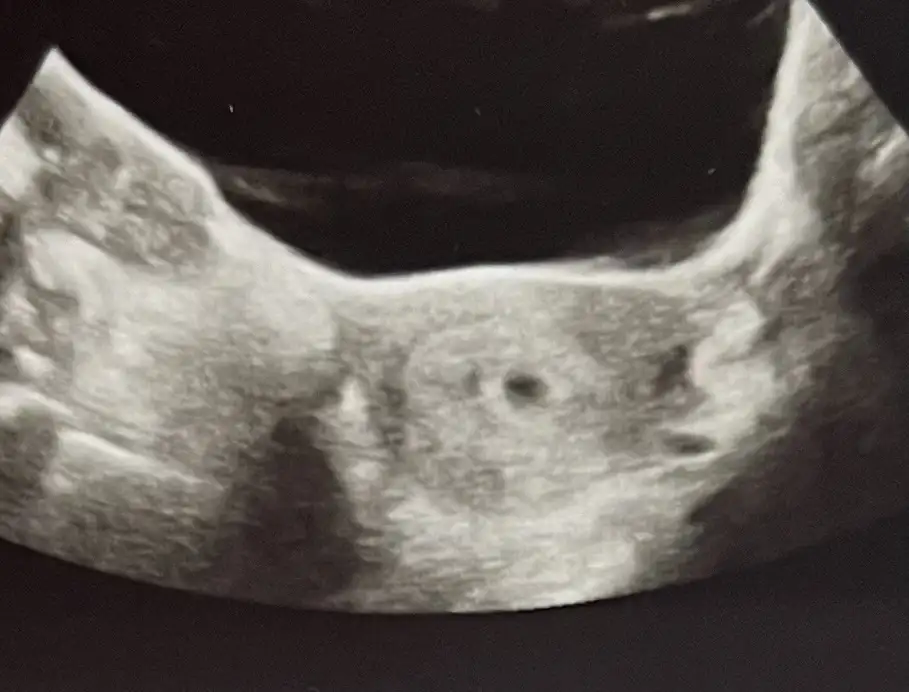

Yaa çok güzel Bi haber darısıda bizlere inşallahKızlar Günaydın ben bugün hastaneye tekrar gittim devlet hastanesine 5+5 ve bebisi gördük şükür darısı hepinize

Ayyy maşallahKızlar Günaydın ben bugün hastaneye tekrar gittim devlet hastanesine 5+5 ve bebisi gördük şükür darısı hepinize